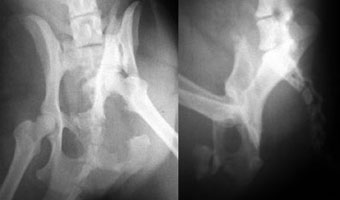

体重11kgの犬。

左側腸骨と坐骨で骨折していました。

腸骨はプレート法で、坐骨はプレート法とピンニングの併用で整復固定しました。

写真上段: 手術前

骨盤の一部が割れて内側に変位しています。

写真下段: 手術後 |